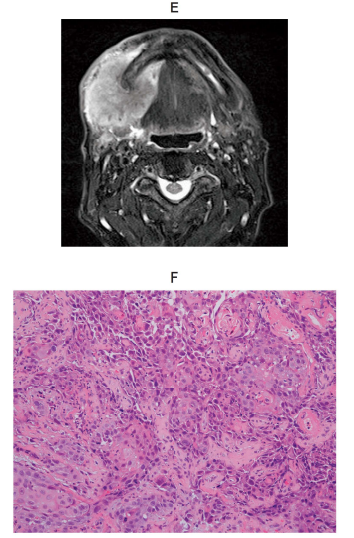

118回 A-30

80 歳の女性。上顎右側歯肉の腫脹を主訴として来院した。 2 か月前から徐々に増大してきたという。15 年前に脳梗塞を発症し、10 年前から関節リウマチと骨粗鬆症で投薬を受けている。初診時の口腔内写真(別冊No. 7A)、エックス線画像(別冊No. 7B)、造影 CT(別冊No. 7C)、FDG-PET/CT(別冊No. 7D)及び生検時のH-E 染色病理組織像(別冊No. 7E)を別に示す。

病変の誘因と考えられるのはどれか。 1 つ選べ。

解答:b

解説:

関節リウマチの薬といえば、メトトレキサート。

メトトレキサートの長期投与により、メトトレキサート関連リンパ増殖性疾患が引き起こされる。

Eの病理組織像を見ると、リンパ球の増殖、異型リンパ球がみられる。